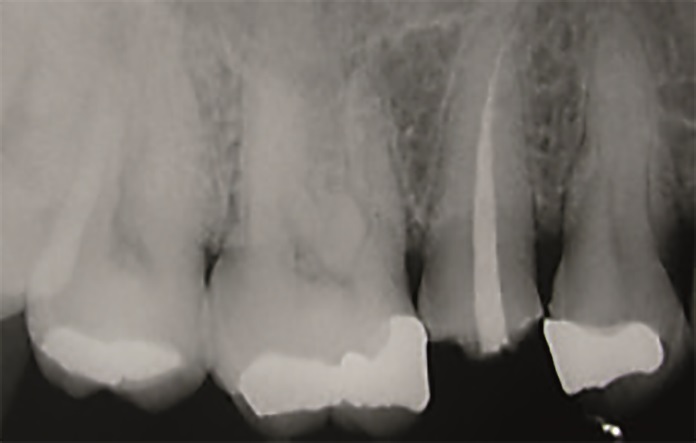

47‑letnia pacjentka zgłosiła się z powodu objawów zapalenia miazgi zęba 15. W badaniu wewnątrzustnym stwierdzono obecność starego wypełnienia amalgamatowego oraz złamanie guzka policzkowego zęba 15 (ryc. 1 i 2). W związku z tym na pierwszej wizycie przeprowadzono leczenie endodontyczne zęba 15 w znieczuleniu miejscowym (ryc. 3).

Obraz kliniczny po przeprowadzonym zabiegu i zdjęcie rentgenowskie przedstawiono na ryc. 22, 23, 24.